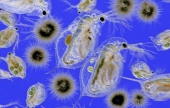

Levenhuk 870T — надежный тринокулярный биологический микроскоп, с помощью которого производится весь спектр наблюдений как в светлом, так и в темном поле. Широко используется в медучреждениях разного типа для урологических, дерматологических, биологических, биохимических, патологоанатомических, цитологических, гематологических и общеклинических лабораторных исследований. А поскольку это тринокуляр, то в комплекте с камерой-окуляром его можно без проблем использовать в качестве цифрового микроскопа. Цена: 650 000 тг. |